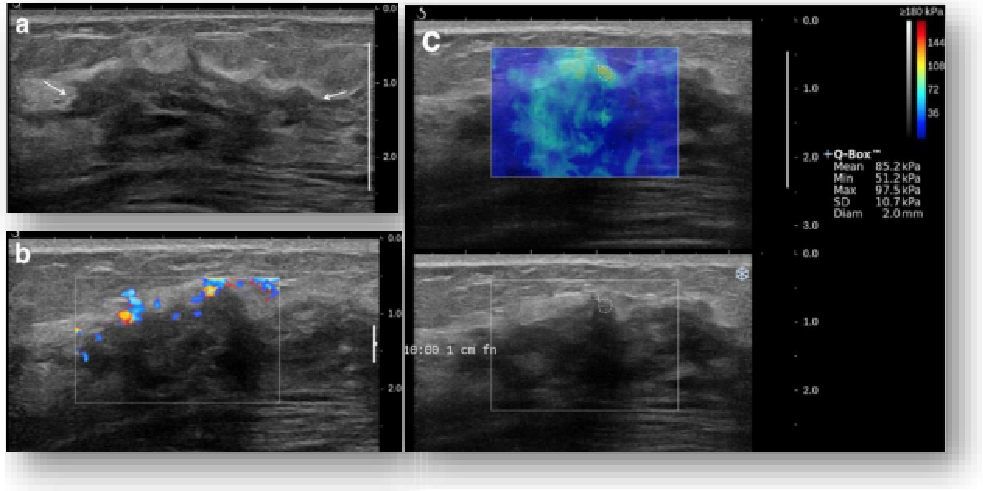

实时剪切波弹性成像

评估组织的软硬,并且提供定量数值,从而提示组织的良恶性。

image.png

鉴别诊断、精准分级、定量评价、穿刺引导、疗效评估、随访观察

恶性占位常常向周边组织进行侵润及扩散,二维很难观察到浸润部分的边界。使用实时剪切波成像能够对占位及周边组织进行硬度评估,通过颜色编码来区分不同组织的硬度信息,直观的观察占位组织的边界信息,更方便区分占位组织和正常组织的边界,准确评估消融范围。

左图病例所示:

钼靶阴性,B型发现非肿块病变

剪切波弹性成像见明确的硬度增高区域。

穿刺及手术病理结果:浸润性导管癌(IDC)

非肿块型病变:B型图像无法确认病变范围,E成像帮助发现异常区域和评估